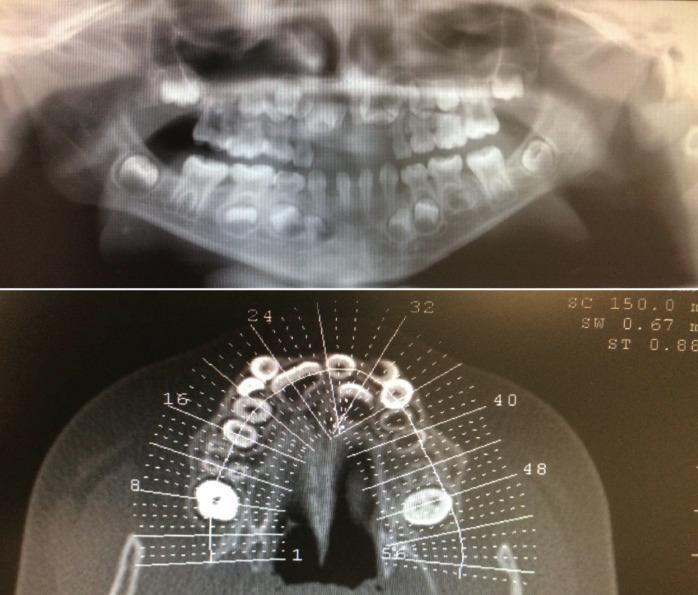

Ellis-van Creveld syndrome (EVC) or chondroectodermal dysplasia is an autosomal recessive disorder, characterized by dwarfism, polydactyly, hypoplastic fingernails and congenital heart defects, finding in most of the cases orofacial anomalies. We describe a clinical case of a 9 year old male patient diagnosed with EVC who visited our Maxillofacial private consultation at Alcorcon Southern Hospital, presenting typical oral manifestations such as dental agenesis, delayed eruption, hypoplasia of the enamel, dental dysmorphism, taurodontism and supernumerary teeth. EVC syndrome is a rare disease and requires a multidisciplinary approach. Oral features are constant and requires the jointly performance of Odontologist and Maxillofacial surgeon aiming to get an appropriate treatment sequence surgery-orthodontics in order to achieve a suitable functional result to improve the quality of life of these patients. Ellis-Van creveld syndrome, chondroectodermal dysplasia, oral manifestations, craniofacial manifestations.

埃利斯-范克里维尔德综合征(EVC)或软骨外胚层发育不良是一种常染色体隐性疾病,其特征为侏儒症、多指(趾)畸形、指甲发育不全和先天性心脏缺陷,多数病例还伴有口面部异常。我们描述了一例9岁男性患者的临床病例,该患者被诊断为EVC,前来我们位于阿尔科孔南部医院(Alcorcon Southern Hospital)的颌面私人诊所就诊,表现出典型的口腔症状,如牙齿缺失、萌出延迟、釉质发育不全、牙齿形态异常、牛牙症和多生牙。EVC综合征是一种罕见疾病,需要多学科方法进行治疗。口腔特征较为固定,需要牙科医生和颌面外科医生共同协作,制定合适的治疗顺序,即先手术再正畸,以获得理想的功能效果,提高这些患者的生活质量。埃利斯-范克里维尔德综合征、软骨外胚层发育不良、口腔表现、颅面部表现